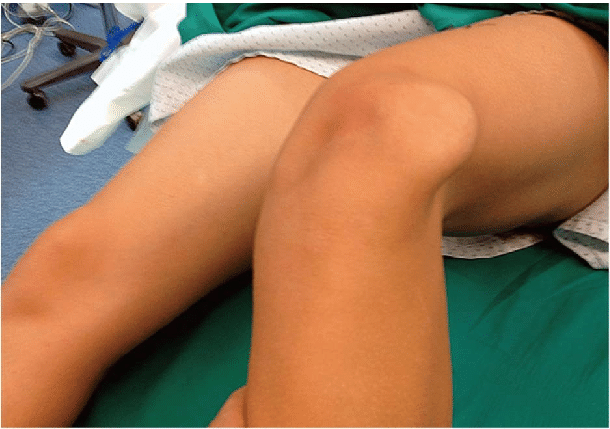

Ως εξάρθρημα ορίζεται η μετατόπιση της επιγονατίδας εκτός θέσης από τη μηριαία τροχιλία. Αυτό συνήθως συμβαίνει συνεπεία ενός βίαιου τραυματισμού με στροφική κάκωση (π.χ πτώση, αθλητικός τραυματισμός) και αφορά στην πλειοψηφία εφήβους και νεαρότερα σε ηλικία άτομα.

Σχεδόν πάντα η επιγονατίδα εξαρθρώνεται επι τα εκτός της μηριαίας τροχιλίας και είτε ανατάσσεται αυτόματα μετά την έκταση του γόνατος από τον ίδιο τον ασθενή είτε με κατάλληλους χειρισμούς στο νοσοκομείο.